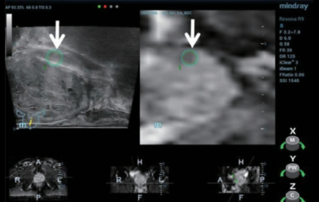

Female pelvic floor anatomy, which developed since the early 20th century, has had a variety of theories, including integral theory, three levels of vaginal support theory, "hammock hypothesis", and three-chamber system. Supporting structures such as pelvic floor muscles, fascia and ligament play an important role in maintaining the normal function of pelvic floor, among which levator ani muscle group is one of the most important supporting structures.